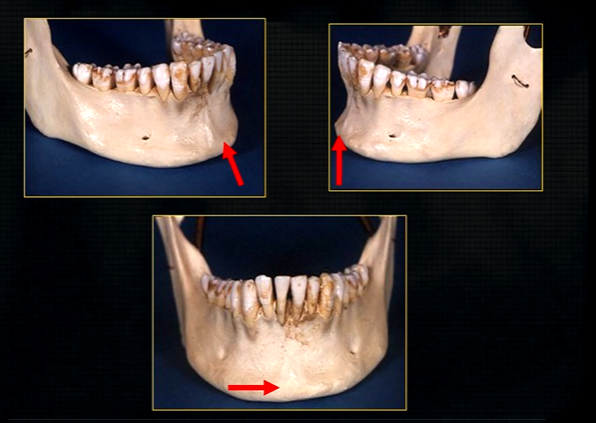

periapical region

can see honeycombed pattern

mental foramen - black radiolucency - near 1st and 2nd premolars

sockets of the teeth are represented by thin, white, opaque lines → ‘ lamina dura’

dense, white, radiopaque line → dense bone of mylohyoid ridge

underneath mylohyoid ridge - looks more radiolucent → this is due to the lingual indentation of submandibular fossa

dense cortical bone of the lower border

radiolucent shadow created by the lingual pit

lower occlusal

small bony spurs of the genial tubercles